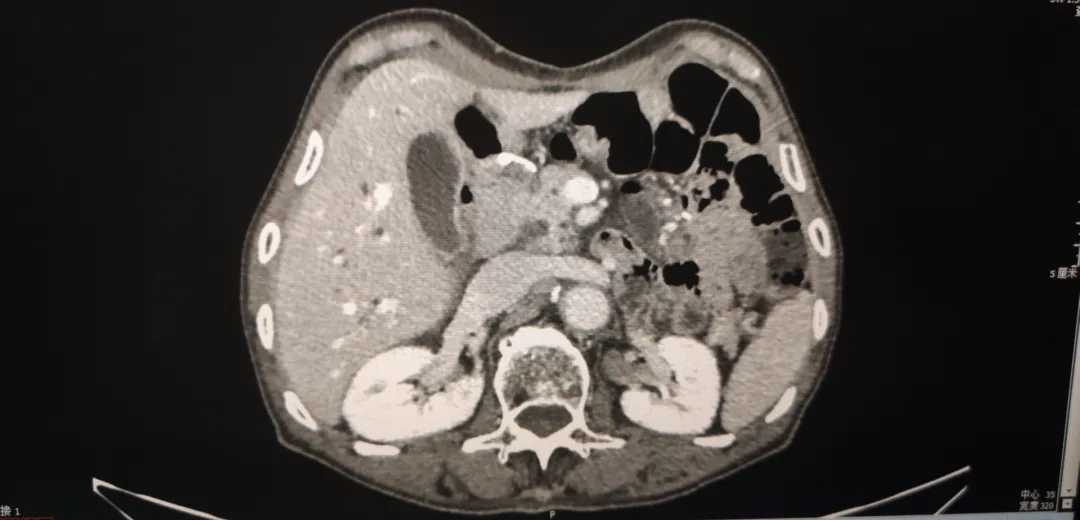

图1-1  2018-4-4  箭头为胃周肿大淋巴结

图1-2 2018-4-4 箭头为胃部肿瘤,胃壁增厚明显

腹盆腔强化CT(2018-4-4):1、胃体及胃窦胃壁增厚,考虑胃癌;2、胃周、胃左动脉区及腹膜后多发肿大淋巴结,考虑转移;3、肝内胆管结石,肝内胆管轻度扩张;4、左肾囊肿,左肾上腺增厚,考虑增生;5、前列腺增生伴钙化;6、盆腔少量积液;7、两下肺实变索条,左侧胸腔少量积液。